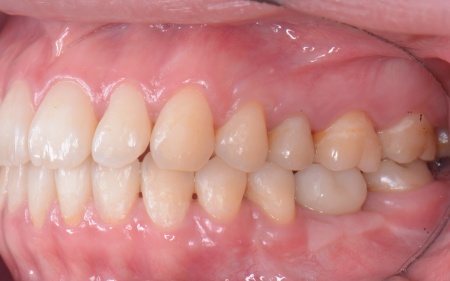

患者様は「健康な歯をできるだけ守りたい」との理由から、③のインプラント治療を希望されました。 まず、右上と左下の奥歯を抜歯しました。 矯正がある程度進んだ段階で、右上と左下のインプラント手術を実施しました。 インプラント手術後は矯正治療の仕上げを行い、装置を外しています。 治療終了後、下前歯の間に見られる三角形のすき間(ブラックトライアングル)が気になるとのご相談がありました。 |

| カウンセリング | 拝見したところ、右上と左下の奥歯に強い痛みが出ていました。 レントゲンで確認した結果、どちらも歯の根が割れていることが判明しました。 歯の根が割れたまま放置すると噛むときの痛みが続くだけでなく、炎症が広がって周囲の歯や骨にまで影響を及ぼすおそれがあります。 また、上下の歯を噛み合わせた際に前歯が噛み合わず隙間ができる開咬(かいこう)と呼ばれる噛み合わせも見られました。 以上のことから、抜歯後に歯を補う治療と噛み合わせを改善するための治療が必要と診断しました。 |